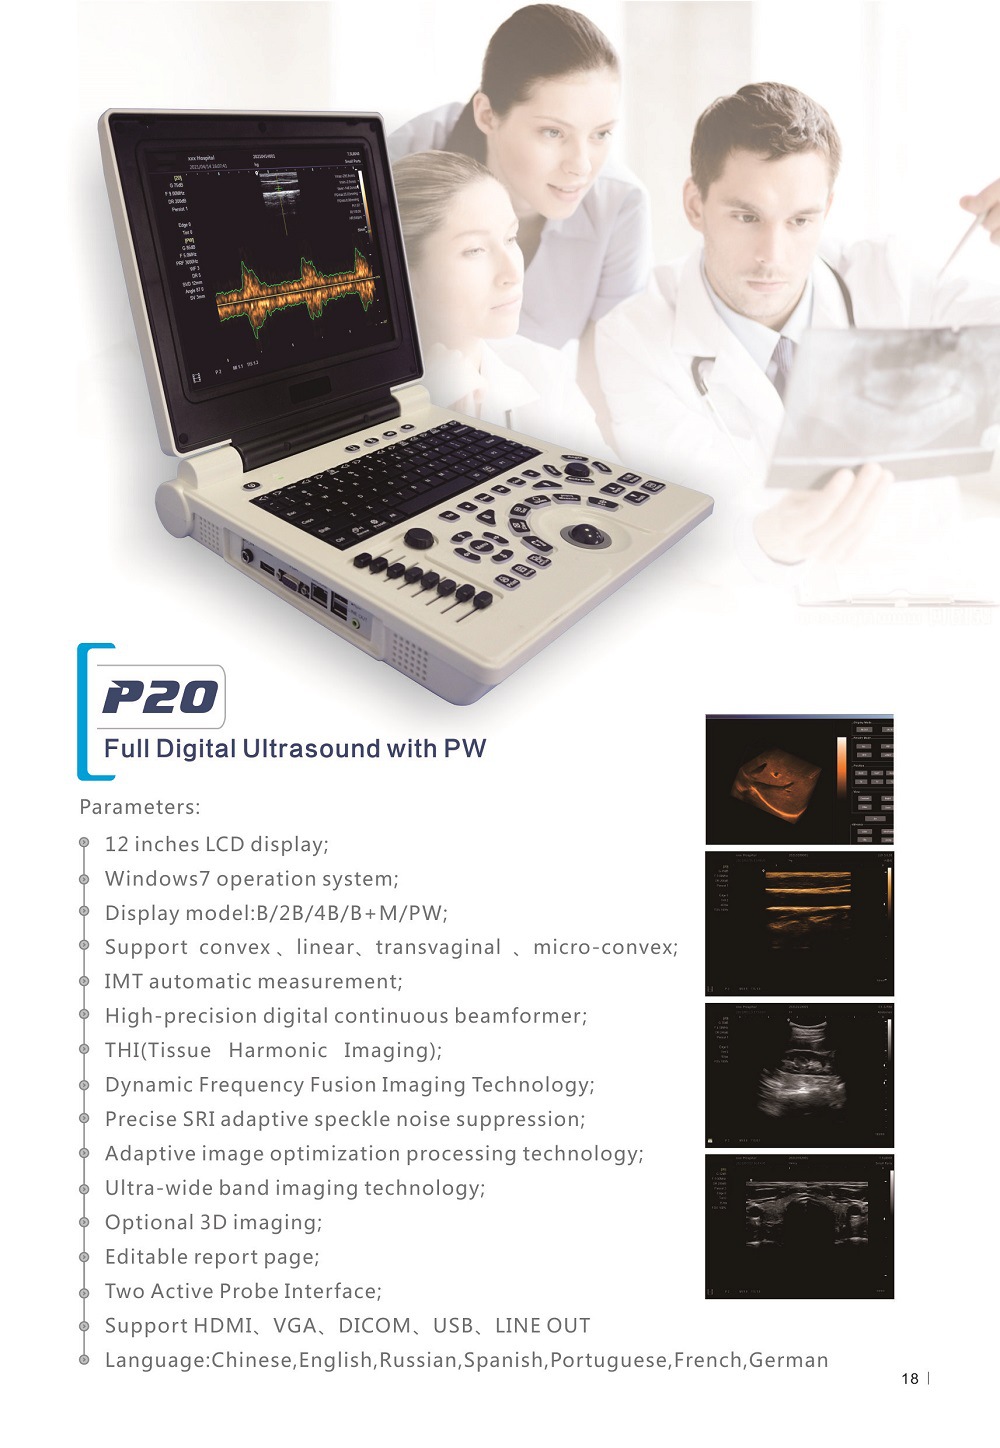

Портативный ультразвуковой аппарат Animal B; Выпуклый массивный зонд; Линейный зонд; Слегка выпуклый зонд; ректальный зонд